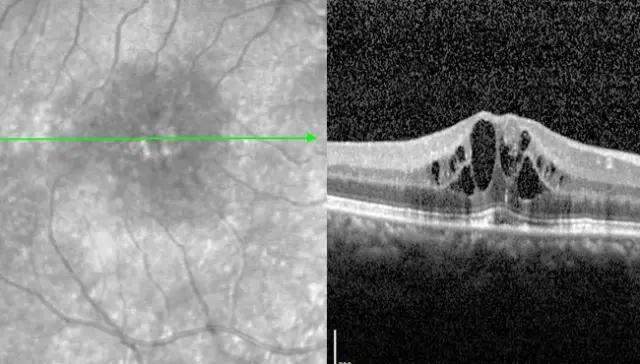

Als vooral het centrum van het gezichtsvermogen is aangetast, spreken we van diabetische maculopathie. Heel vaak is er sprake van oedeem in het centrale netvlies, d.w.z. vochtophoping in het netvliesweefsel. Getroffen patiënten lijden een aanzienlijk verlies van hun centrale gezichtsscherpte. Lasertherapie wordt zelden overwogen in het gebied van de macula - want als de fovea centralis, ons gezichtscentrum, wordt aangetast, is de nevenschade van de laserstraling groter dan het therapeutische voordeel.

In het geval van DMO, zoals bij natte AMD of vaatafsluiting, worden daarom zeer vaak VEGF-remmers overwogen, die kunnen worden toegediend als onderdeel van een IVOM (intravitreale toediening van geneesmiddelen). In tegenstelling tot veel andere ziekten wordt de anti-VEGF-therapie voor diabetisch maculair oedeem gestart met een reeks van 6 injecties met maandelijkse tussenpozen (in plaats van 3 injecties), omdat het oedeem bij diabetes meer tijd nodig heeft om op te lossen.